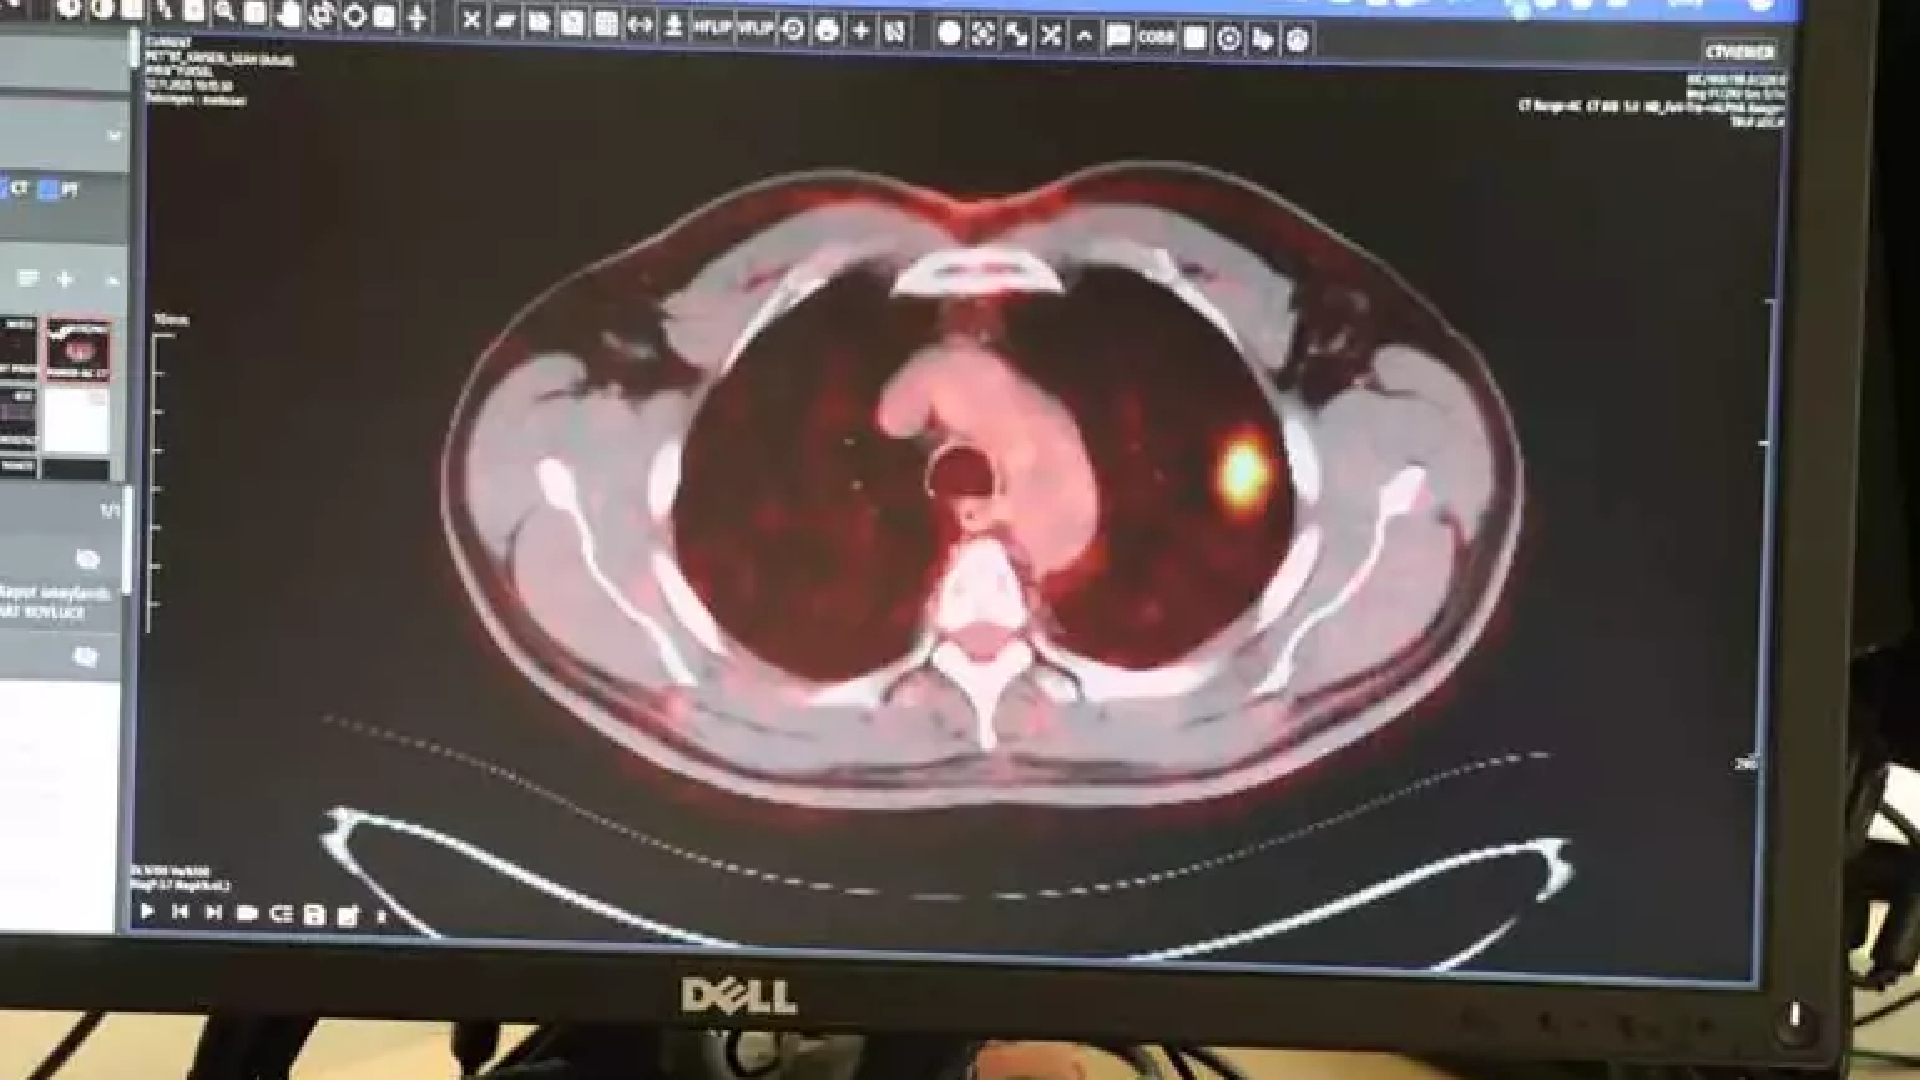

Kayseri Şehir Hastanesi Göğüs Cerrahisi Kliniği’nde görev yapan Doç. Dr. İbrahim Ethem Özsoy ise “Akciğer kanseri, dünya genelinde 2 milyon 200 bin civarında insanı etkiliyor. Bunlardan 1 milyon 800 bini de vefat etmekte. Türkiye geneline baktığımızda ise yılda 45-50 bin civarında akciğer kanseri vakası bildirilmekte. Akciğer kanserinde en önemli şey erken teşhis. Bazı hastalarda bizim hastamızda olduğu gibi erken evrelerde tesadüfen saptanıyor. En önemli hastaneye başvuru bulguları göğüs ağrısı, nefes darlığı, öksürükle ya da balgamla karışık kanlı balgam ve diğer sistemlerini etkilediyse uzak organ belirtisiyle hastalarımız gelebiliyor. Akciğer kanserlerinin yüzde 90 civarında kısmı sigarayla ilişkili ya da sigarayı bırakmış kişiler. Hastamız da 61 yaşında. 50 yıldır sigara içen bir hasta ve düzenli olarak da kontrollere giden bir hasta. Acil servisimizde çekilen tomografide yaklaşık 2 santimlik küçük bir nodül görülmüş. Biz bunu incelemeye aldığımızda kanser olduğunu tespit ettik” dedi.

Akciğer kanserinin 4 evreden oluştuğunu aktaran Doç. Dr. Özsoy, “Bunlarda kendi içinde gruplara ayrılır. Evre 1 ve 2 hastalar sınırlı hastalık olarak geçer ve cerrahiye uygundur. Evre 3’te çok az bir kısmı cerrahi yapılabilir. 100 hastaya akciğer kanseri tanısı koyuyorsanız ancak 20 tanesi cerrahiye uygun olarak karşımıza çıkıyor. Geri kalan yüzde 80’i ileri aşamalarda karşımıza çıkıyor ve cerrahi şansını kaybetmiş oluyor. Hastamız, erken evrede teşhis konulup tedavi edildiği için bundan sonra yaşamına normal bir şekilde devam edecek. Hiçbir kısıtı olmayacak. Muhtemelen kemoterapi bile almayacak. Uzun yıllar sigara içip de belli yaşın üzerine gelen hastalarımızın mutlaka yılda 1 defa akciğer tomografisi çektirmesi gerekiyor. Çünkü küçük lezyonlar akciğer grafisinde görünmeyebiliyor” diye konuştu.(DHA)